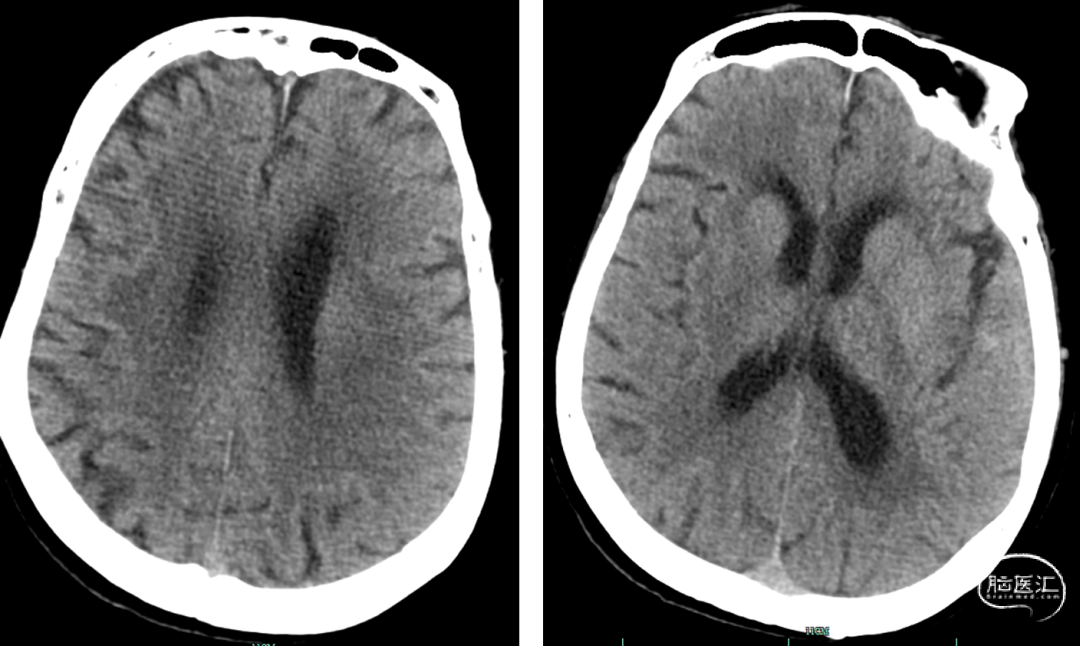

术后DynaCT,有少量造影剂外渗。予速尿针、白蛋白针、甘露醇针脱水预防脑水肿,阿司匹林肠溶片、抗血小板,强化他汀治疗。

术后复查头颅CT:无明显出血等表现。